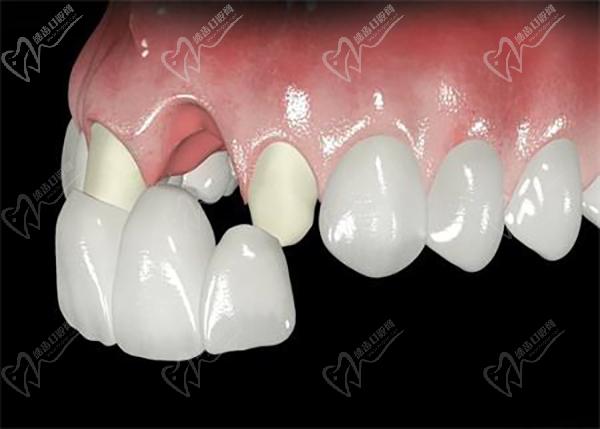

廣州柏德口腔主打德系口腔,引進德國先 進的口腔診療設備和技術。 注重數(shù)字化技術應用,提供更可靠的診療服務。 擁有一批經(jīng)驗豐厚的醫(yī)生團隊,擅長處理各種復雜的口腔問題。注重3D數(shù)字化種植技術,術前種植牙方案模擬和設計更準。也側重數(shù)字化正畸技術,矯正過程更精 準高 效。